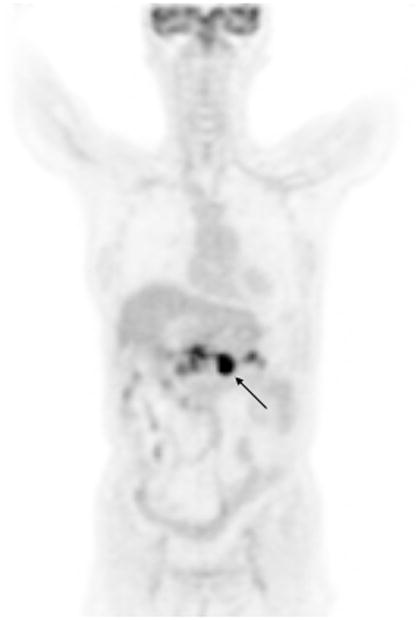

Figure 3.

Coronal FDG PET Image of a patient with pancreatic adenocarcinoma. Although the malignant tumor involving the body of the pancreas (black arrow) was confirmed by histopathology, the fainter areas of increased activity in the pancreas adjacent to this tumor can represent either tumor infiltration or pancreatitis, since inflammation of the pancreas may also lead to increased FDG uptake in the pancreas.

The main limitation of PET may be the lack of anatomical detail to determine surgical resectability, specifically vascular infiltration and invasion of surrounding organs. Another limitation may be in differentiating benign inflammatory processes from malignancies (Figure 3). Strobel et al42, in considering pancreatic cancer resectability, determined that PET was able to detect metastases to the liver, lung, and bone but failed to detect arterial infiltration in all 5 patients with known tumor infiltration of the celiac trunk or superior mesenteric artery. Sendler et al37 showed that PET falsely identified 4 of 7 patients with chronic pancreatitis to have malignant disease. The potential for false positive PET findings resulting from non-malignant pancreatic diseases should also be a topic for further research.